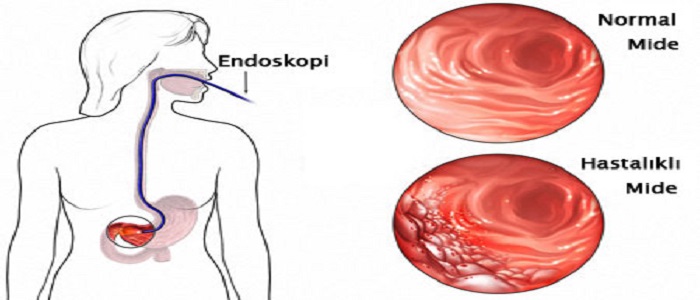

Kanserin hangi aşamada olduğuna, hastanın yaşına ve sağlık durumuna göre farklı tedavi türleri uygulanabilmektedir. Öncelikle midenizle ilgili bir şikayetiniz varsa, ya da size mide kanseri teşhisi konulmuşsa gastroenterolog, cerrah ve medikal onkologlardan tedaviniz hakkında bilgi alabilirsiniz. Mide kanserinde tercih edilen tedavi yöntemleri ağırlıklı olarak ameliyat (cerrahi müdahale) olmak üzere, kemoterapi ve radyoterapi gibi metodlardır.

Kanserin hangi aşamada olduğuna, hastanın yaşına ve sağlık durumuna göre farklı tedavi türleri uygulanabilmektedir. Öncelikle midenizle ilgili bir şikayetiniz varsa, ya da size mide kanseri teşhisi konulmuşsa gastroenterolog, cerrah ve medikal onkologlardan tedaviniz hakkında bilgi alabilirsiniz. Mide kanserinde tercih edilen tedavi yöntemleri ağırlıklı olarak ameliyat (cerrahi müdahale) olmak üzere, kemoterapi ve radyoterapi gibi metodlardır.

- Cerrahi Tedavi: Mide kanseri tedavisinde en çok tercih edilen cerrahi tedavi şeklidir. Bu yöntemle öncelikle tümörün yeri, büyüklüğü, diğer organlara sıçrama ihtimali gibi durumlar hesaplanır ve ona göre hareket edilir. Genellikle göbeğin üst kısımdan açılan kısımdan midenin bir bölümü veya tamamı çıkarılarak alınmaktadır. Ameliyatın bu şekline gastrektomi adı verilir. Eğer midenin bir kısmı alındıysa kısmi gastrektomi, midenin tamamı alındıysa total gastrektomi denmektedir. Ameliyat sonrasında hasta kendini bir süre yorgun ve halsiz hissedebilir, kabızlık veya ishal gibi bağırsak düzeninizin bozulduğu durumlar görülebilmektedir. Bu gibi yan etkiler görüldüğünde endişeye kapılmamalı, eğer çok şiddetli ağrı ya da daha başka yan etkiler görürseniz hemen ameliyatınızı yapan doktorunuza danışmalısınız.